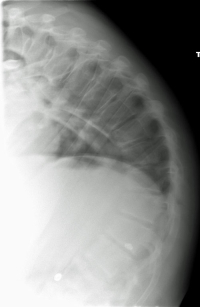

(Click to Enlarge Image) This is an AP X-ray (scoliogram) of a patient with severe scoliosis. The white line depicts the center of gravity line from the head. It should intersect the center of the pelvis. The black horizontal line demonstrates how far off the patients balance is. The amount of energy expended necessary to walk made her use a walker for balance.